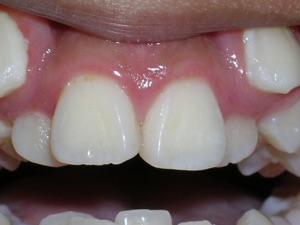

Here’s an example from a young boy who had very significant crowding. One can see that the canines on top and bottom are blocked out. There was also an overbite. The combination made the case challenging. Watch.